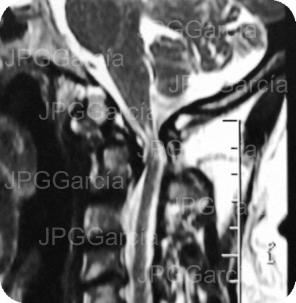

Imágenes de resonancia de la unión cráneo cervical que muestra mielopatía cervical compresiva severa